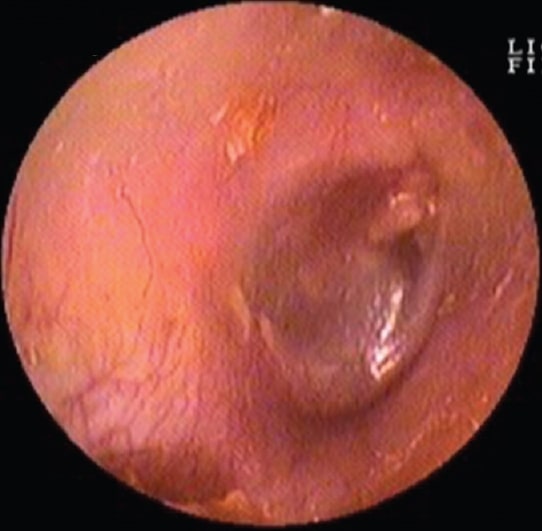

Perforations of the tympanic membrane can come in different shapes and sizes due to a wide variety of causes. Complicated cases requiring an underlay procedure are oftentimes performed in the OR and under general anaesthesia. Even with successful procedures, residual or recurrent perforations may occur. For these (revision) cases which are limited in size (alike some primary perforations), a full OR facilitated procedure is not necessary. A transcanal overlay during an in-office procedure under local anaesthesia will suffice. In these cases, EpiPatch offers a biological patch that serves as a bandage and covering to protect the surgical area.